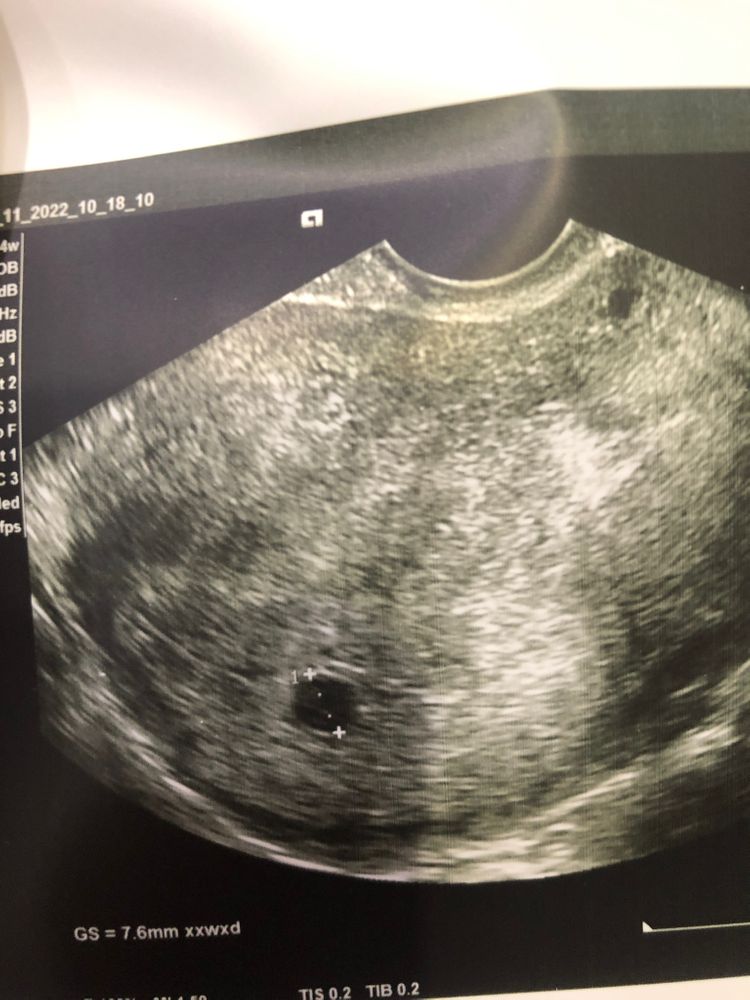

Оксана, что у вас в итоге? Оба развиваются? У меня тоже два пя было на прошлом узи, но одно меньше гораздо и сказали скорее всего рассосется. Вот через неделю иду на узи повторно. Очень хочу двойню.